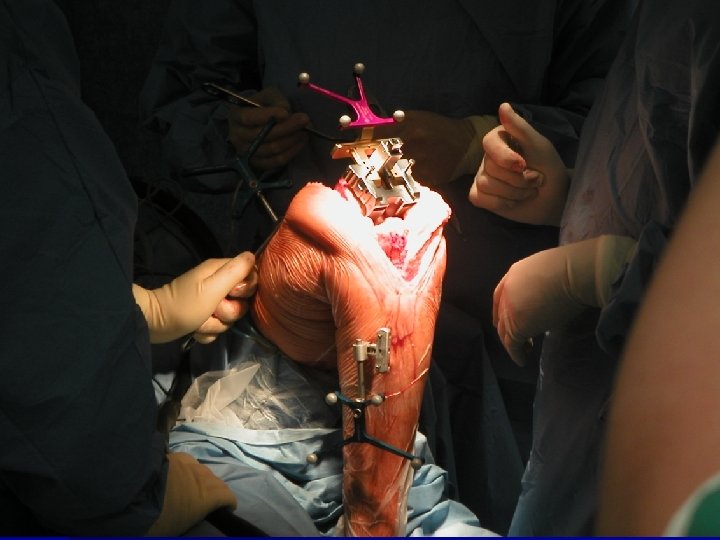

Navigatie

Wat is nodig? Fluoroscopie Software per prothese Detectiesystemen Infrarood camera Computer hardware Chirurgisch team

Hoe werkt het De computer detecteert gedurende heel de ingreep het been van de patiënt , het prothese materiaal en de instrumenten. n Virtuele fluoroscopie n De chirurg opereert n De computer navigeert n